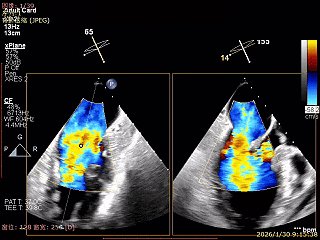

X-Plane切面切2区可见前叶Flail

2区上Color,可见反流来源

X-Plane切面切3区可见前叶脱垂

3区上Color,可见反流来源

3D Enface 2区及3区前叶脱向左房

3D Enface 可见反流由2区3区从前后冲出